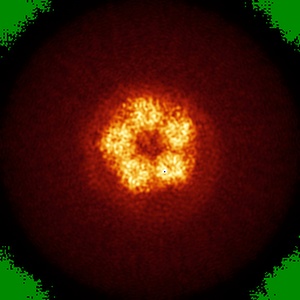

Cyro-EM structure of human Glycine Receptor alpha2-beta heteromer, glycine bound, (semi)open state

Sample: Glycine receptor alpha2-beta heteromer, glycine bound, open state

Characterization of the subunit composition and structure of adult human glycine receptors

Yu H, Bai X-C, Wang W

(2021) Neuron , 109 , 2707 - 2716